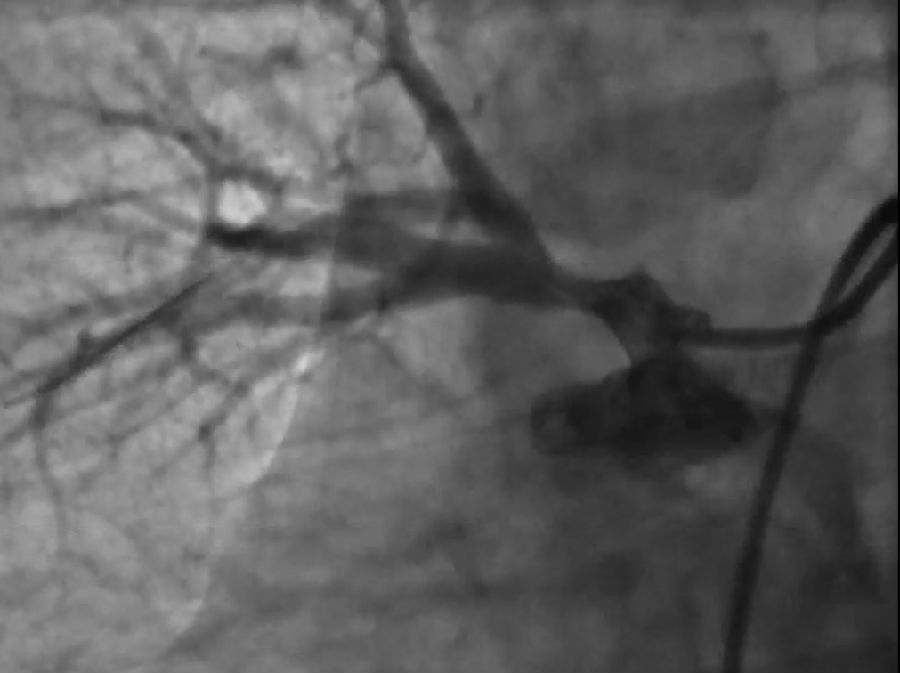

首先选择性肺动脉造影:显示右上肺动脉开口处严重狭窄。